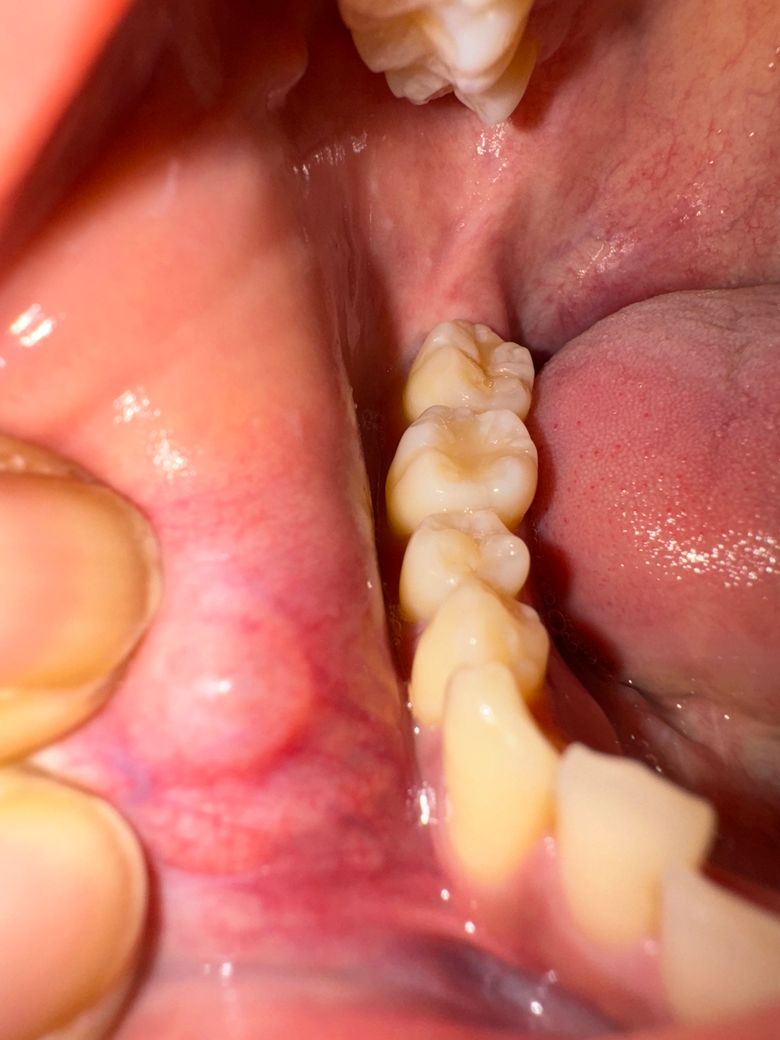

한달 반 전에 치과 두군데 다녀왔는데 a병원에서는 좀 더 지켜보자고 더 커지면 대학병원에 가서 제거하고 조직검사 해보는게 좋겠다고하셨고 b병원에서는 제거해주겠다하시고 재발하면 그 때 다시 제거해서 조직검사해보자고 하셨었습니다. 그리고 오늘 다시 세군데 병원에 갔는데 a병원은 더 커졌다. 구강암은 아닐것같은데 불안하면 대학병원 가서 제거하고 조직검사해봐라. 가능성이 아예 없는것이 아니다. 라고하셨고 b병원은 저번보다 커지긴했으나 병변이 깊고 얕아서 제거할 정도는 아닌것같다. 뭔지는 조직검사해봐야알겠지만 구강암일 가능성은 적으니 두달뒤에 보자 하셨고 c병원은 이비인후과인데 점액낭종일거라고 별말씀 안하셨습니다.

선생님들이 보시기에 제거하고 조직검사를 해봐야하는 정도의 병변일까요? 그렇다면 대학병원을 예약햐야할 것 같아서요.. 고견부탁드립니다.

• 4번 째 사진